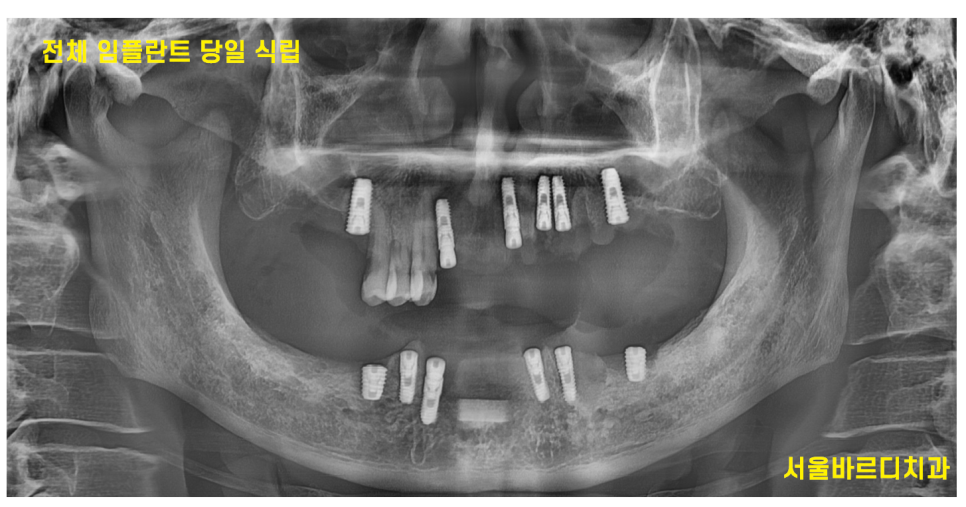

저희 병원은 디지털 방식으로

네비게이션 임플란트를 사용하여 정교하게 진행하고 있는데요.

이 방법은 수술 시간이 짧고 통증을 최소화할 수 있어 환자들의 만족도가 높습니다.

240513

전체적인 치아 치료가 필요하셨던 환자분

진단 결과에 따라 안좋은 치아는 당일 발치 후

전체 임플란트를 식립하셨습니다.

이후, 개개인 맞춤 보철물을 제작해 자연스러운 외형과 기능을 복원하였습니다.